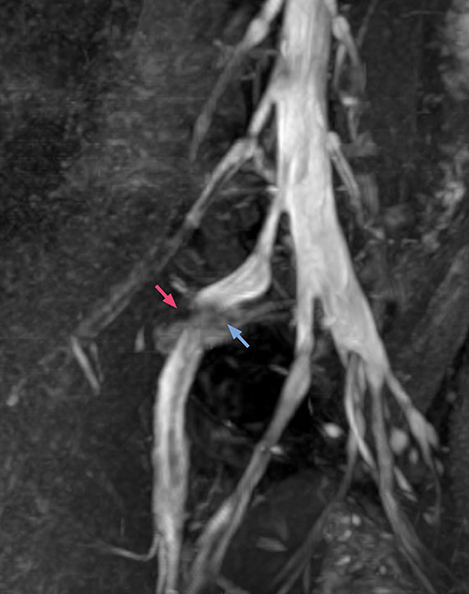

“For example, in sagittal images, when the presence of fat is observed in the intervertebral foramen, it suggests that there is a margin around the nerve. Similarly, the absence of fat indicates that the nerve is being compressed. So, we used to deduce nerve compression indirectly. With NerveVIEW, however, we can observe the condition of the nerves directly, regardless of the presence or absence of fat. We always prefer such direct observation of anatomy over having to make an inference about it.”

“The intra-luminal signal of veins, especially around the intervertebral space, can be suppressed well with NerveVIEW. As a result, we can easily observe the detailed nerve structure around the posterior ganglion,” he says. “This is why we use 3D NerveVIEW for intraforaminal stenosis and extraforaminal stenosis/herniation (lateral disc herniation). On the other hand, if herniation is suspected to exist inside the dorsal root ganglion (DRG), balanced TFE or ProSet-FFE is applied. NerveVIEW is not suitable for evaluating the median type of herniation.” The SE-EPI DWI-based method for MR neurography works well for large FOV exams like whole-body MRI, but focal examination of nerves is often limited by the attainable spatial resolution (both inplane and slice direction) and geometric distortion. “3D NerveVIEW achieves higher in-plane resolution – close to our other routine spine sequences – and the source images can be used instead of adding a fat-suppressed T2-weighted sequence,” Tanji says.

According to Tanji, methods such as ProSet FFE, STIR or 3D VISTA are anatomically nonselective because background signals, for instance from blood vessels, often interfere with nerves, which hampers evaluation of details, especially at the peripheral side of the nerves.